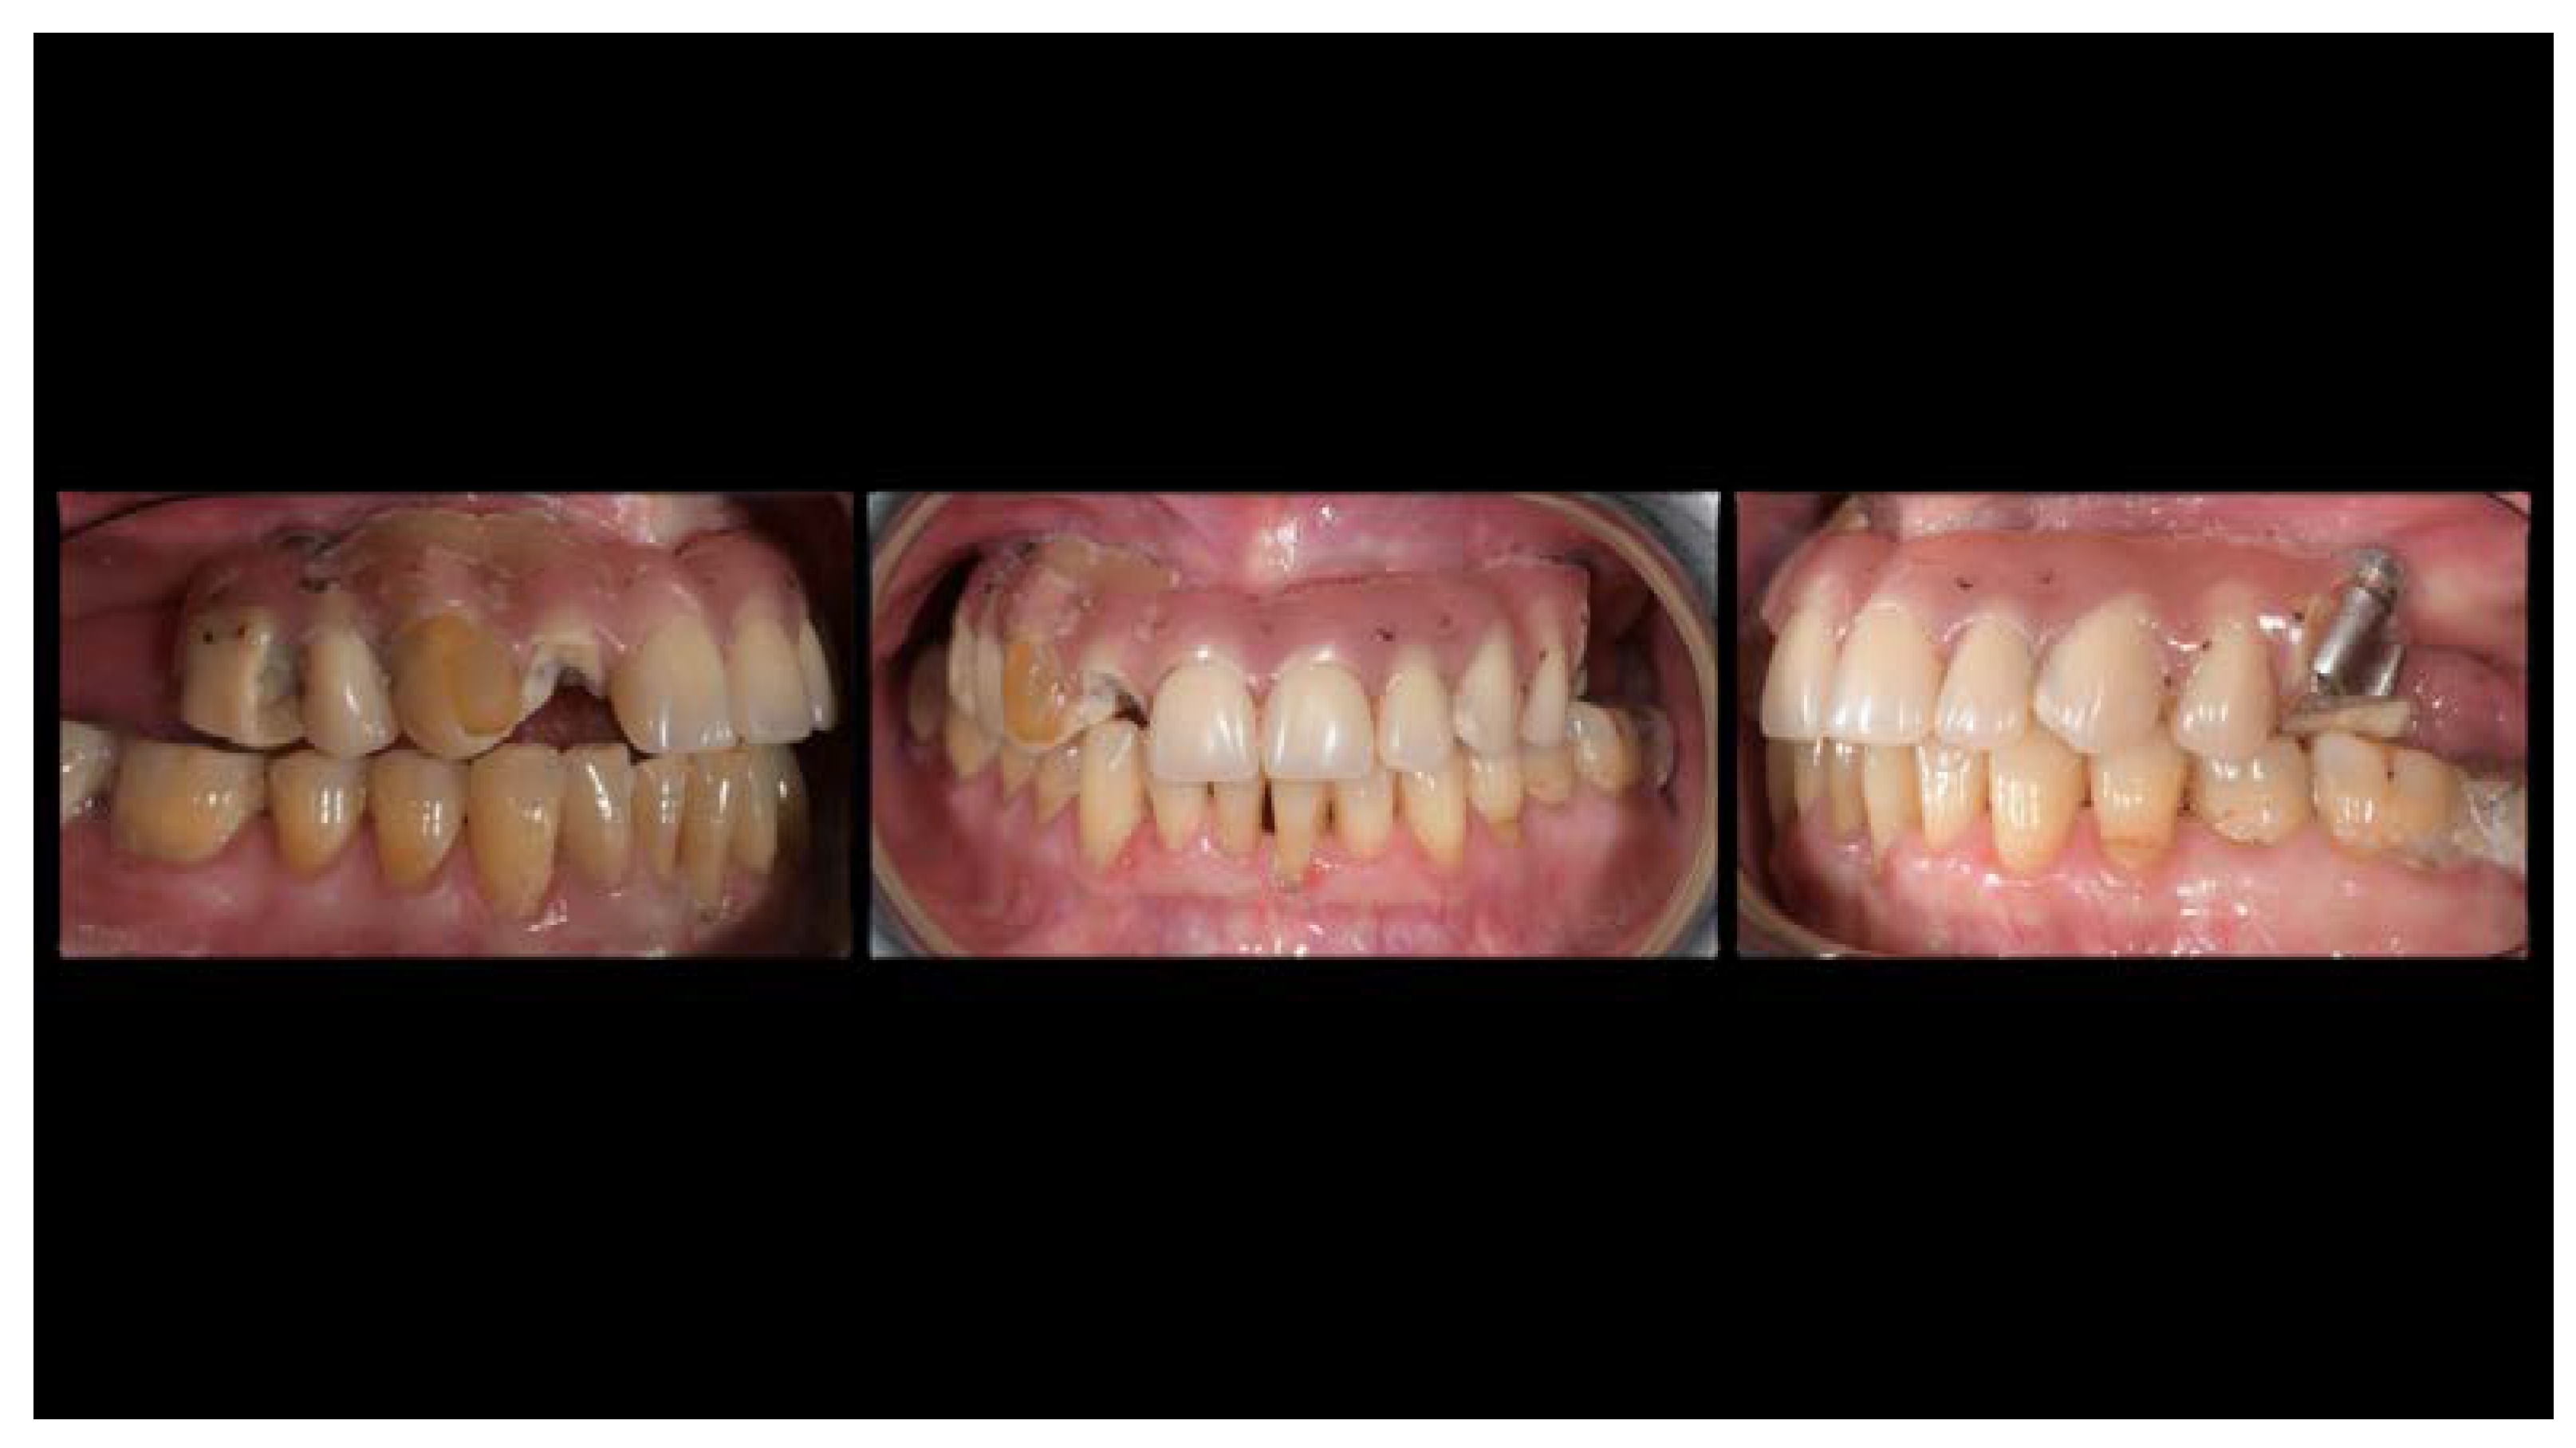

A partially edentulous 78-year-old woman with a complete screw-retained implant-support hybrid prosthesis (Figure 1) in the upper jaw and natural dentition in the lower jaw was referred to a private center in Rome, Italy, due to several continuous breakages of the prosthetic part of the implant-supported rehabilitation. After a preliminary interview, the patient stated that the implant treatment was finished two years before, but she had never been comfortable with this prosthesis (Figure 2). Relevant symptoms were phonetic difficulties, inability to maintain hygiene, and repeated breakages, leading to functional and esthetic issues (Figure 3). After that, the patient’s medical history was collected, and preoperative photographs, radiographs, periodontal screening results, and model casts were obtained for initial evaluation (Figure 4). During the clinical examination, the actual prosthesis was unscrewed, due to teeth detachments, and replaced with the old temporary prosthesis delivered by the patient. Both existing prostheses were evaluated and judged inaccurate, with particular attention to the fit of the prosthesis, the vertical dimension of occlusion, phonetics, facial support, and lip position. All the possible treatment options were then discussed and evaluated together with the patient. The main concerns of maintaining the previously placed implants were some exposed threads and the troubling disparallelism that makes the prosthetic treatment difficult, increasing the risk for biological complications and technical complications, respectively (Figure 5). Nevertheless, the patient refused a complete removable denture, so that implant removal would lead to placement of new implants, in combination with guided bone reconstruction and soft tissue management. This treatment plan may have the risks of implant failure and increased patient morbidity (Table 1 and Table 2). An implant-supported fixed dental prosthesis was initially excluded due to the implant’s disparallelism. Hence, a maxillary implant-supported overdenture was initially considered quite possibly the best therapeutic option.

Figure 1.

Picture of the patient’s work and initial situation.